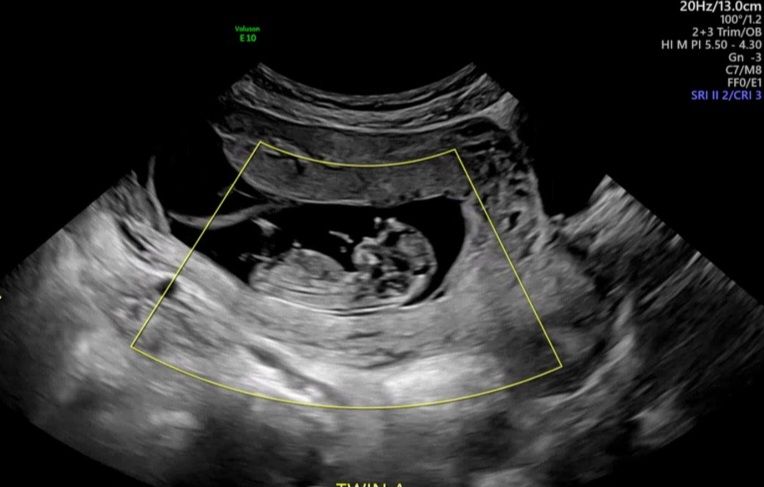

고수님들 12주 각도법 의견 요청드려요

고수님들의 눈썰미를 기대합니다~^^(꾸벅)